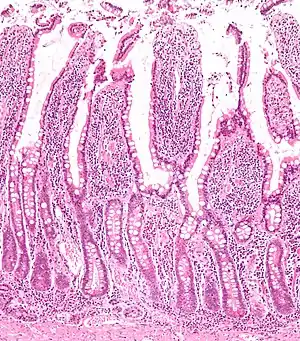

![]() Micrograph of the small intestine mucosa showing the intestinal glands - bottom 1/3 of image. H&E stain. | |

In histology, an intestinal gland (also crypt of Lieberkühn and intestinal crypt) is a gland found in between villi in the intestinal epithelium lining of the small intestine and large intestine (or colon). The glands and intestinal villi are covered by epithelium, which contains multiple types of cells: enterocytes (absorbing water and electrolytes), goblet cells (secreting mucus), enteroendocrine cells (secreting hormones), cup cells, tuft cells, and at the base of the gland, Paneth cells (secreting anti-microbial peptides) and stem cells.

Intestinal glands are found in the epithelia of the small intestine, namely the duodenum, jejunum, and ileum, and in the large intestine (colon), where they are sometimes called colonic crypts. Intestinal glands of the small intestine contain a base of replicating stem cells, Paneth cells of the innate immune system, and goblet cells, which produce mucus.[1] In the colon, crypts do not have Paneth cells.[2]